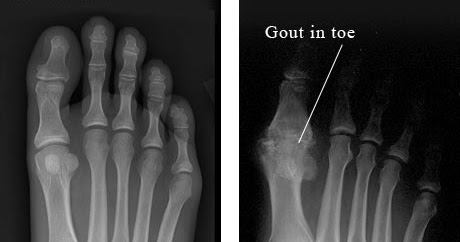

Penyebab kadar asam urat tinggi. Penyakit asam urat terjadi saat kadar asam urat naik sehingga membentuk kristal. 5 jenis obat asam urat pada lutut termanjur.

Daerah yang diserang biasanya pergelangan tangan dan siku, sendi jari kaki, jari tangan, lutut, tumit dan dengkul. Tanda gejala asam urat dimulai dengan rasa panas, gatal, atau kesemutan di persendian satu umumnya, rasa sakit ini terjadi di pankal jempol kaki, siku, lutut, pergelangan tangan atau kaki, hingga punggung kaki. Berikut beberapa cara mengatasi asam urat secara alami dirangkum dari berbagai sumber. Penyakit asam urat kebanyakan menyerang sendi jari tangan, lutut, pergelangan kaki.